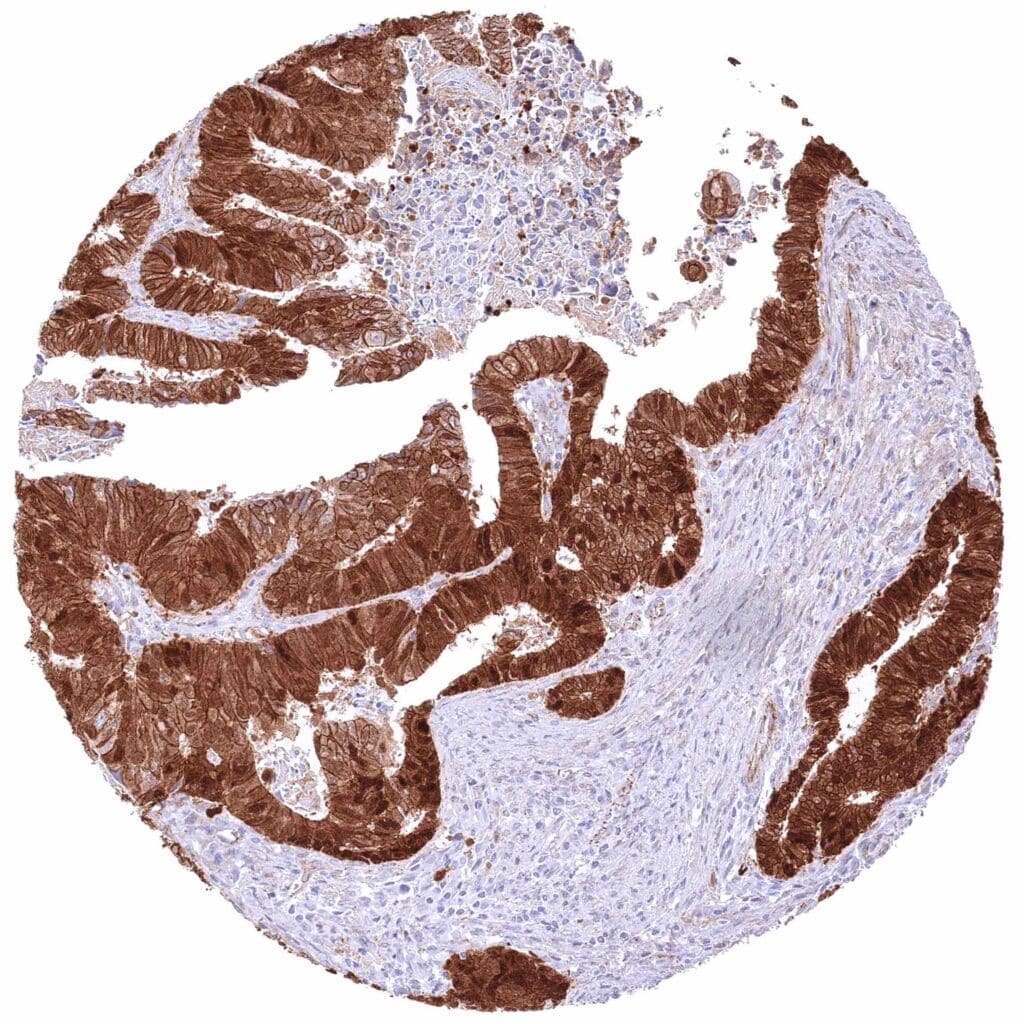

Colon – Colorectal adenocarcinoma with moderate membranous and cytoplasmic but strong nuclear β-Catenin staining of tumor cells.

Colon – Colorectal adenocarcinoma with weak membranous and cytoplasmic but strong nuclear β-Catenin staining of tumor cells.

Colon – Colorectal adenocarcinoma with weak membranous but strong cytoplasmic and nuclear β-Catenin staining of tumor cells.